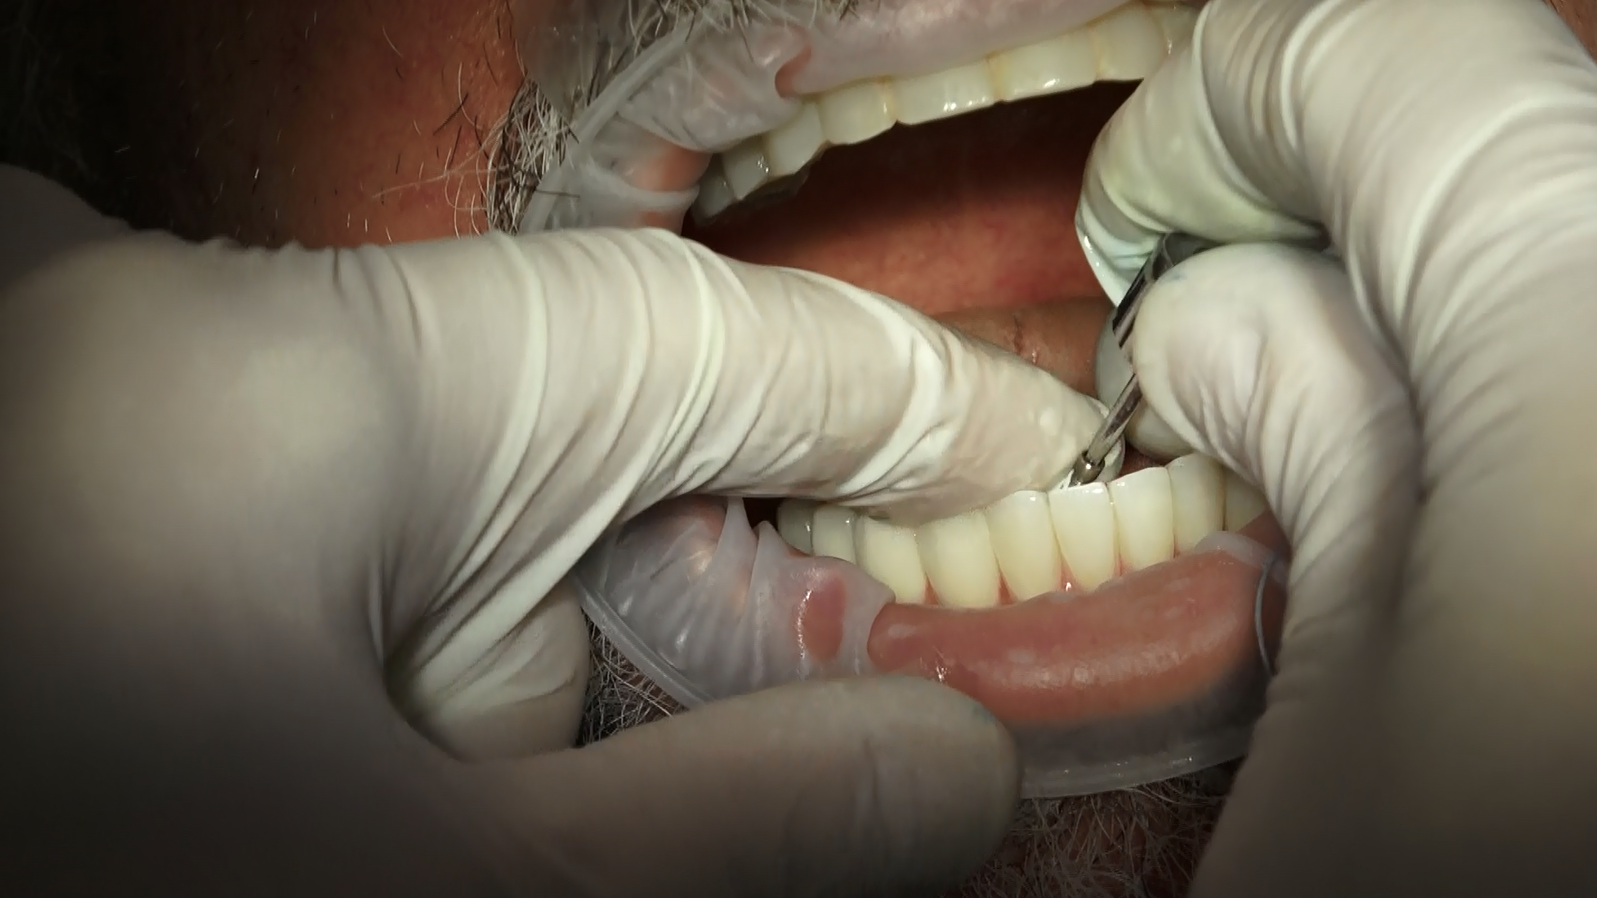

Segue alcune immagini dell’intervento con inseritore della griglia sottoperiostea e protesi fissa provvisoria

Inserimento e Fissaggio della Griglia

La griglia tridimensionale viene posizionata all’interno della mascella atrofica e fissata con piccole viti osteointegrate. Questo fornisce un’ancoraggio solido per la protesi dentale, garantendo stabilità e durata nel tempo.